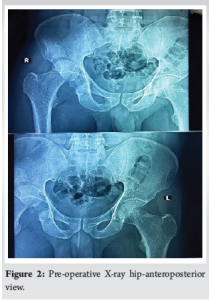

Radiology

X-rays and computed tomography (CT) scan confirmed a neglected posterior dislocation of the right hip with a comminuted fracture of the acetabulum involving the posterior wall and column (Fig. 1-7). The femoral head showed early degenerative changes.